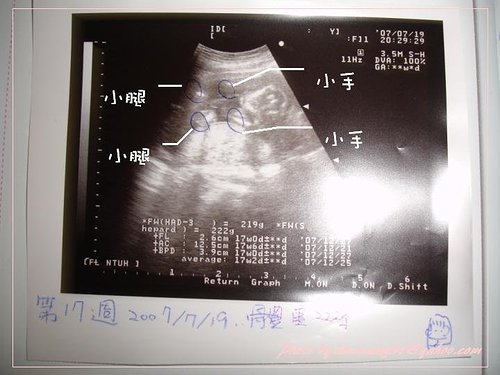

7/19 第17週 的產檢

這次醫生有量寶寶的手長、腿長喔~醫生說我的寶寶有220克了,屬於正常大小喔